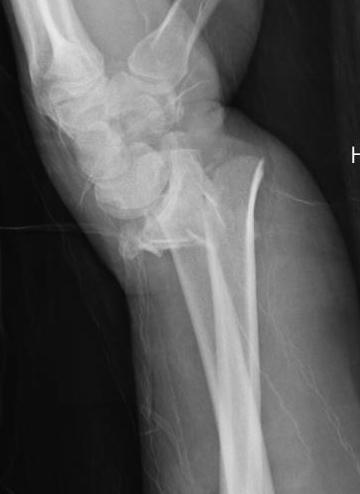

Colle's Fracture

- distal radial fracture with dorsal displacement